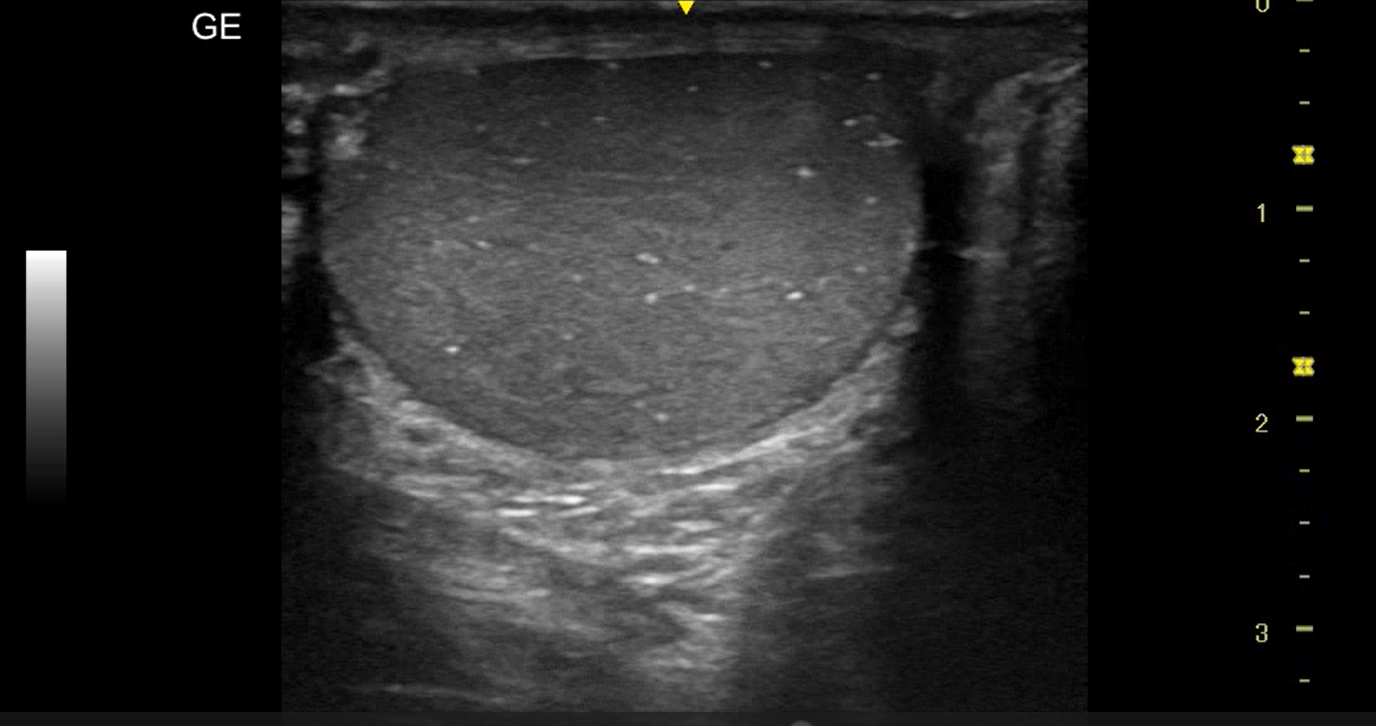

Realizamos ecografía clínica testicular: observamos ambos testículos con microlitiasis bilaterales puntiforme sin sombras acústicasen, en forma de cielo estrellado, vascularización normal, cabeza epidídimo izquierdo con leves signos inflamatorios, mínimo hidrocele.

La ecografía testicular reglada testicular realizada al mes presenta resolución de orquiepidimitis y confirma microlitiasis testiculares.

La microlitiasis testicular es una entidad poco frecuente que se detecta de forma incidental durante una ecografía realizada por otros motivos como el caso de nuestro paciente. Se ha asociado con un mayor riesgo de desarrollar cáncer testicular y alteraciones de la fertilidad, como a otras patologías urológicas, como el varicocele, hidrocele, la orquiepididimitis, anomalías relacionadas con el síndrome de disgenesia testicular y el pseudoxantoma elástico. La ecografía es una herramienta diagnóstica esencial en atención primaria para la detección de las diferentes  patologías testiculares.